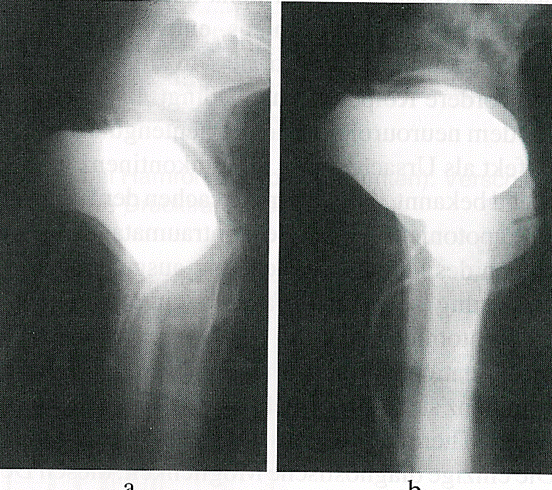

Diagnostik

Röntgenuntersuchung der Blase